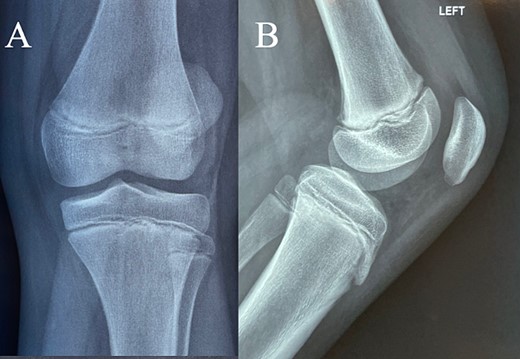

At the local hospital, the patient underwent X-ray examination of the affected knee and was subsequently immobilized with an above knee cast. The X-rays yielded normal results (Fig. 1). Instructions were provided to restrict weight-bearing, and a follow-up examination was scheduled in 10 days. However, the family presented to our facility, instead.

(A + B) Antero-posterior and lateral X-ray examination of the injured knee. Radiological examination shows no fracture.